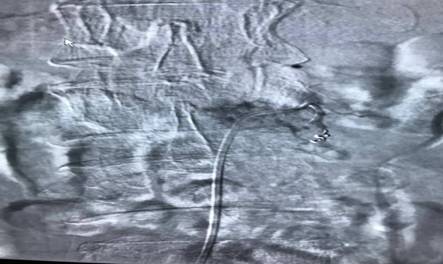

患者劉先生,54歲,患肝癌16個(gè)月,因腰腿痛伴下肢麻木4月余入住中心醫(yī)院脊柱外科。腰椎MRI顯示腰2椎體轉(zhuǎn)移腫瘤、椎管占位、神經(jīng)根受壓,PECT顯示腫瘤單節(jié)段椎體侵犯、椎弓根骨折。手術(shù)指針明顯。為最大限度地挽救患者的神經(jīng)功能,改善其生活質(zhì)量,脊柱外科決定為其施行手術(shù)切除減壓。術(shù)前,蘇光輝、汪向東二位主任帶領(lǐng)科室技術(shù)骨干與腫瘤科尹忠文主任、血管外科涂宏主任、麻醉科段雪琴主任多次會(huì)商術(shù)前計(jì)劃,經(jīng)周密術(shù)前準(zhǔn)備后,術(shù)前當(dāng)天由血管外科先行瘤體血管栓塞術(shù),以減少術(shù)中出血,栓塞手術(shù)非常成功,手術(shù)按時(shí)進(jìn)行。術(shù)中蘇光輝主任、汪向東副主任與肖華斌、陳威副主任醫(yī)師為其施行腫瘤椎體全切術(shù)。術(shù)中出血量在2000ml以內(nèi),出血量的控制超出手術(shù)團(tuán)隊(duì)的預(yù)期。手術(shù)相當(dāng)順利,術(shù)后患者快速康復(fù)出院。

脊柱腫瘤手術(shù)治療一直是脊椎外科的熱點(diǎn)難點(diǎn),也頗具爭(zhēng)議,因其手術(shù)創(chuàng)傷大、解剖結(jié)構(gòu)復(fù)雜,特別是難以控制的大出血常常導(dǎo)致手術(shù)失敗,甚至危及患者生命。此次脊柱外科與腫瘤內(nèi)科、血管外科、麻醉科緊密合作。采取術(shù)前栓塞,術(shù)中控制性降壓,為脊柱全切術(shù)創(chuàng)造了良好條件,也為多科合作聯(lián)合開(kāi)展高難度手取得了成功經(jīng)驗(yàn)。

腫瘤血管栓塞前造影圖片

腫瘤血管栓塞后造影圖片